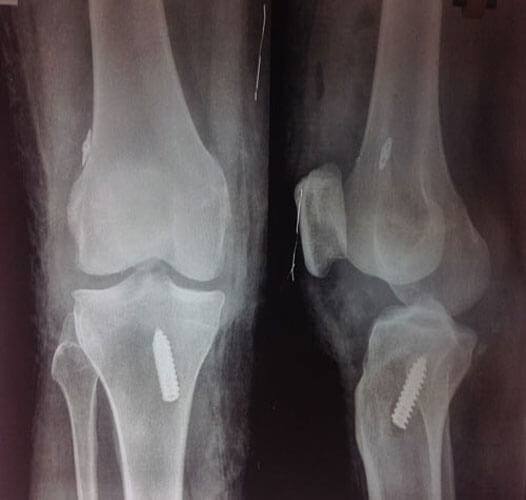

Arthroscopy Surgery